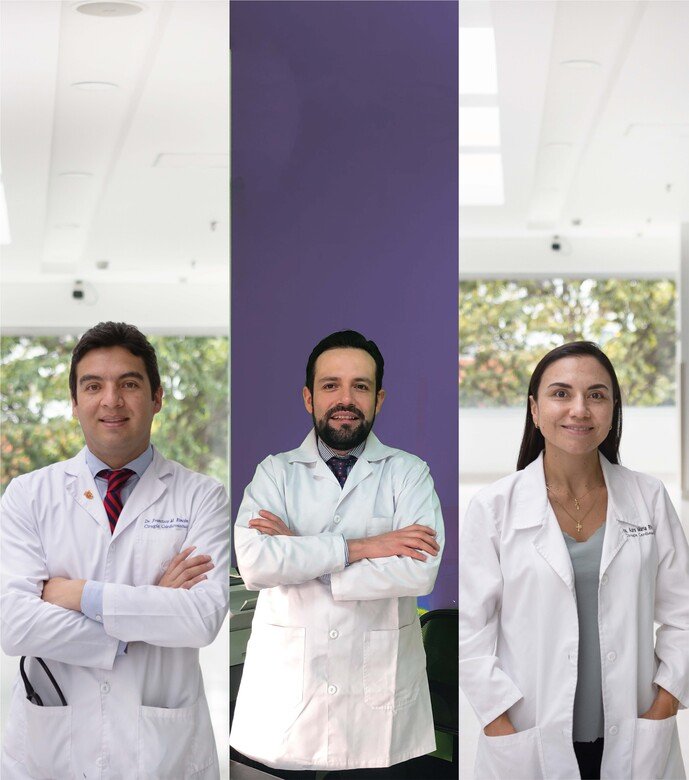

Somos especialistas en ofrecer a nuestros pacientes una combinación única de rehabilitación de alta calidad con turismo en un destino atractivo como lo es la Capital de Colombia. Nos enorgullece conectar a nuestros clientes con los mejores doctores especializados en ortopedia, cardiología, tórax y muchas otras áreas médicas.

Trabajamos en estrecha colaboración con prestigiosos centros médicos y expertos en rehabilitación para brindar tratamientos personalizados y una recuperación eficiente.

Contamos con Cirujanos Cardiovasculares, Cirujanos Ortopédicos, Cirujanos de Tórax y Cáncer de pulmón.

Contamos con Cirujanos Cardiovasculares, Cirujanos Ortopédicos, Cirujanos de Tórax y Cáncer de pulmón.

Nos destacamos por una atención integral con programas personalizados. Nuestro equipo altamente calificado garantiza excelencia en cada aspecto de la atención.